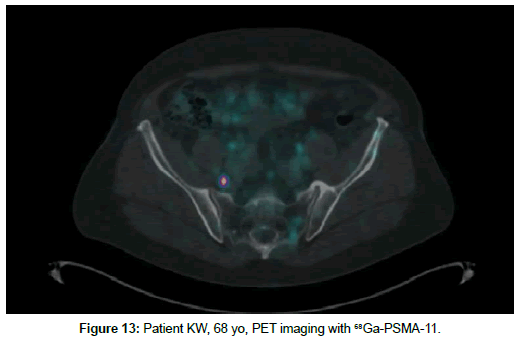

Patient KW, 68 yo, prostate cancer treated with radiotherapy in 2014, biochemical relapse during suppressive therapy with PSA 0,94 ng/ml on 29th December 2016. First PET scan 21th April 2017 positive at pelvic lymph node, with no bone uptake (Figures 11 and 12). Due to rising seric PSA to 31, 88 ng/ml a second PET with 68Ga- PSMA was carried out on 15 September, with confirmation of lymph node metastasis and multiple pathologic bone foci not present at choline imaging (Figures 13 and 14).